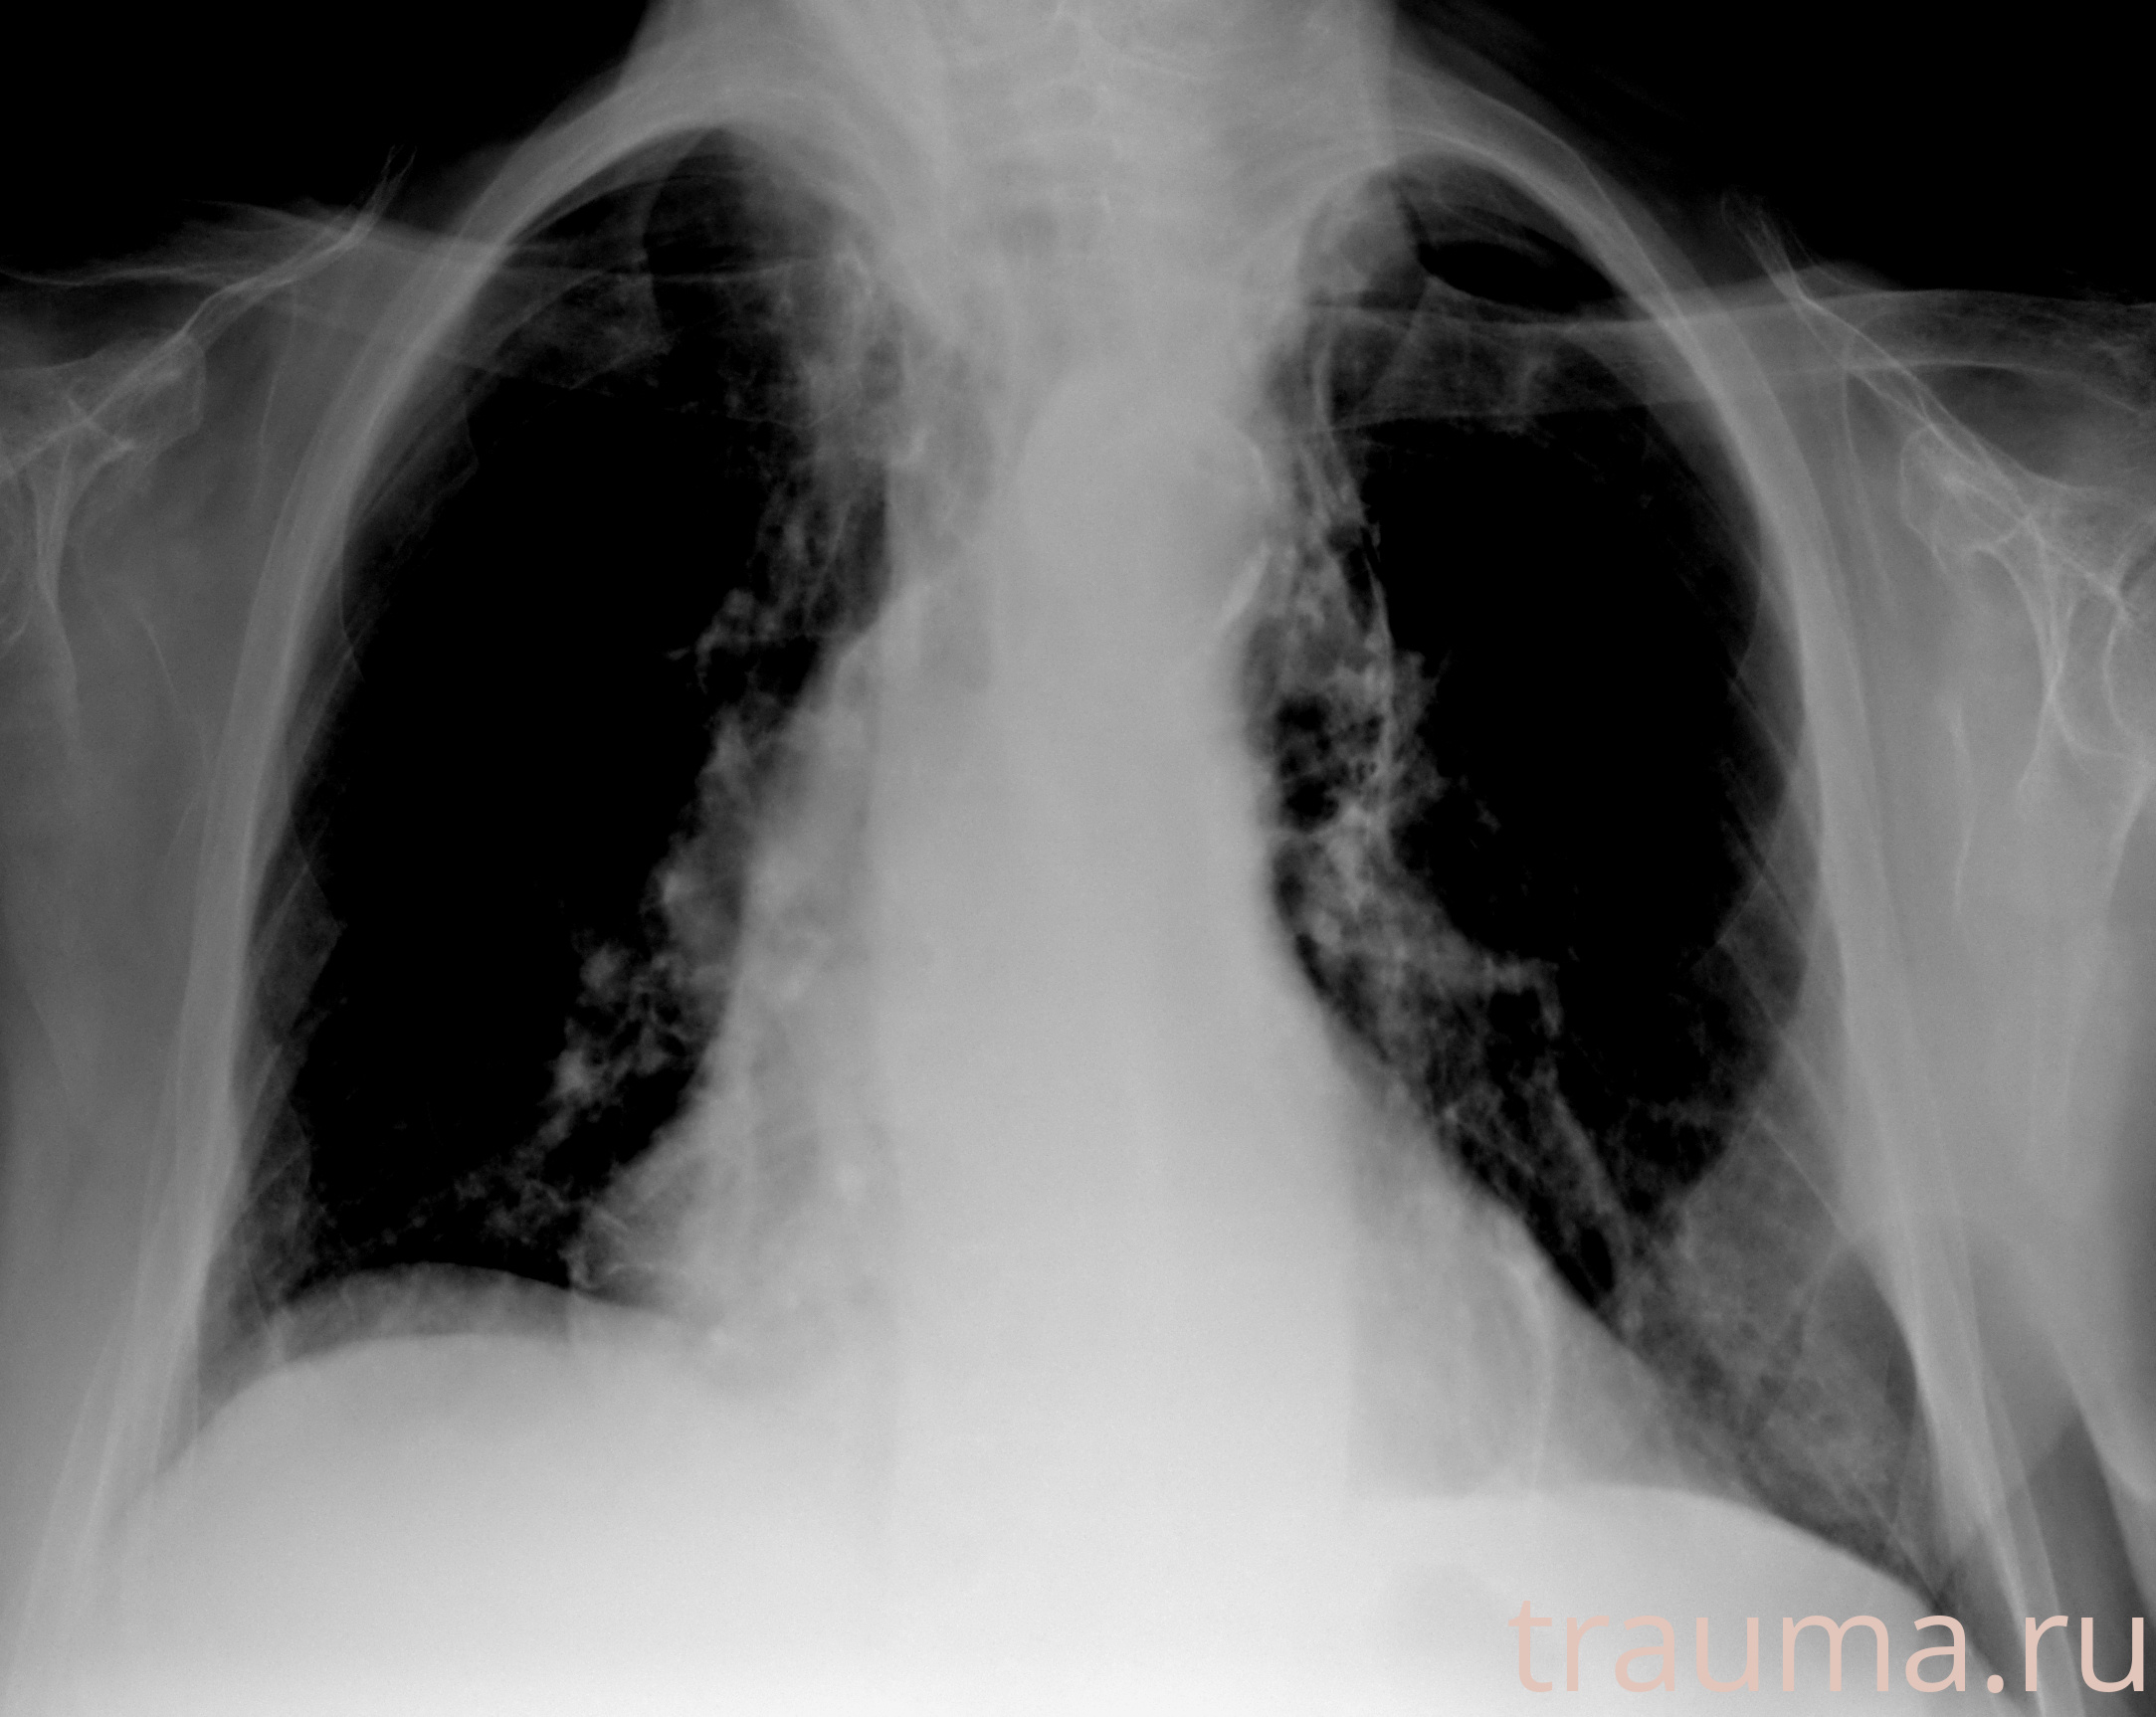

Рентгенограммы

Рентген на дому: по вашему адресу приезжает врач-рентгенолог, травматолог-ортопед с мобильным рентгеновским аппаратом, проводит диагностику травмы или заболевания, делает необходимые рентгенограммы, дает рекомендации по дальнейшему лечению. Получить качественные снимки в домашних условиях возможно благодаря уникальной методике, разработанной МосРентген Центром для института  Склифосовского

при переломе шейки бедра и пневмонии от компании МосРентген Центр - партнера Института имени Склифосовского

Яркость: 1   Контраст: 1   Инвертировать: 0 Увеличение: 1

Перетаскивайте мышь вверх/вниз для контраста, влево/право для яркости. Прокрутка колесом изменяет масштаб. Нажмите Сбросить для возврата к исходному изображению. При увеличении держите мышь в той области, которую хотите рассмотреть.